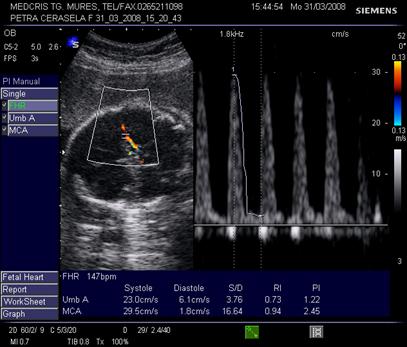

Doppler pe artera ombilicala

Daca fasciculul Doppler ("poarta") este bine centrat, sunetul este optim si spectrul este caracteristic pentru artera din cordonul ombilical. Linia de baza trebuie sa separe fluxul arterial de cel venos.

Derularea benzii cu spectrul Doppler va "curge" pana cand exista parametrii de calitate:

sunet caracteristic

minim 5 cicli consecutivi, identici, bine conturati, deasupra liniei de baza

fluxul venos continuu este sub linia de baza

Fig. nr.321. Spectru Doppler normal pe artera ombilicala